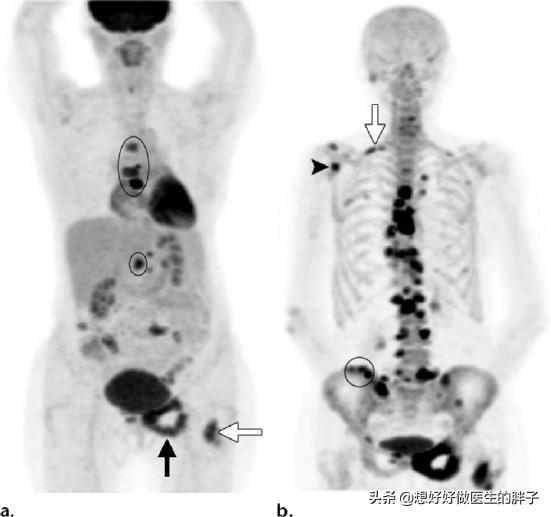

がんの既往歴がなく、家計に余裕がある患者には、全身にがんの疑わしい病変がないかスクリーニングするためにPET-CT検査を行うことが推奨され、これにより腫瘍病変の有無、進行度、どのような転移病巣があるかなどを適切に判断することができる。

がんの既往があり、その時点で悪性度が高いと判断されれば、全身骨シンチで骨転移の有無を調べることができる。同時に、転移部位の骨破壊の程度を磁気共鳴検査で明らかにすることができる。

症状があるから病院に検査に行き、医師はCTを勧めるが、患者は面倒に感じたり、費用がかかると感じたりして、通常のレントゲンを選択することが多い。通常のX線検査による腫瘍診断の感度は44~50%と非常に低く、CTによる骨転移診断の感度は71~100%、MRIの診断感度は82~100%、PET_CTによる腫瘍検出の感度は92%、特異度は99%に達し、これらのデータの違いは一目瞭然である。。